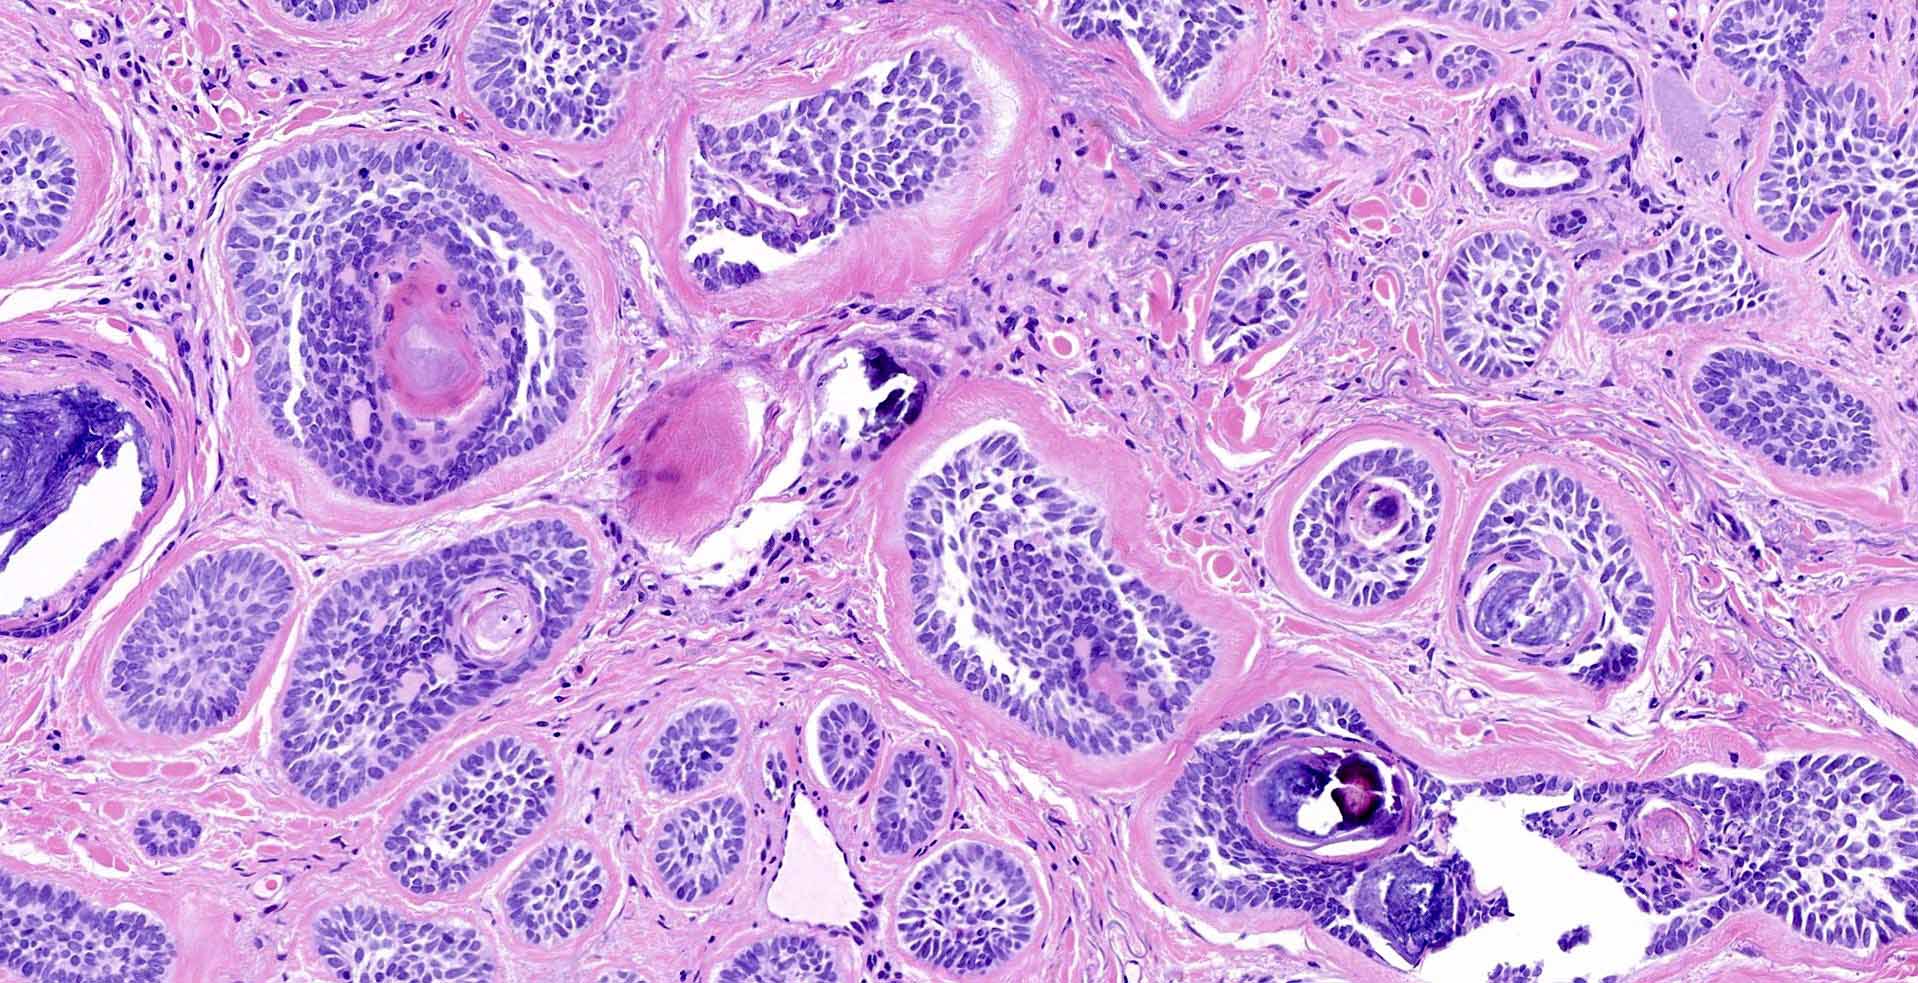

Гистология базалиома